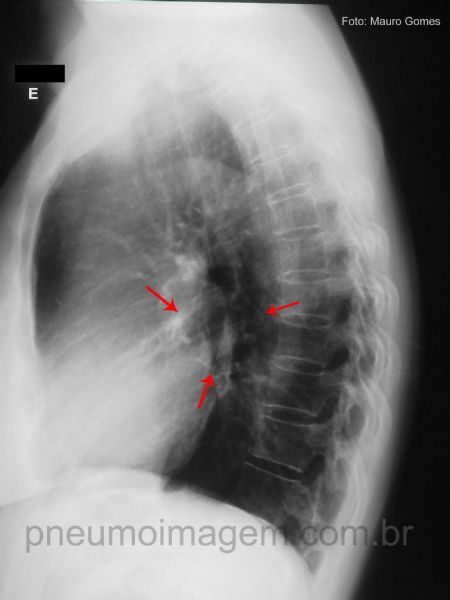

Ao perfil, observe a seta mostrando toda a tênue linha que delimita a circunferência do cisto. Os cistos broncogênicos são revestidos por epitélio colunar ciliado ou epitélio cubóide e estão rodeados por tecidos semelhantes aos do brônquio normal, incluindo cartilagem, músculo liso, tecido elástico e glândulas mucosas.

Detalhe da incidência em perfil demonstrando a tênue linha que delimita a circunferência do cisto.